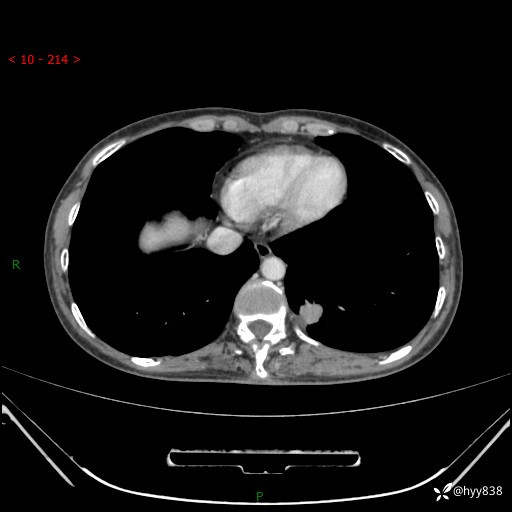

胸部CT平扫

增强动脉期+静脉期

各期CT值:48hu 65hu 76hu